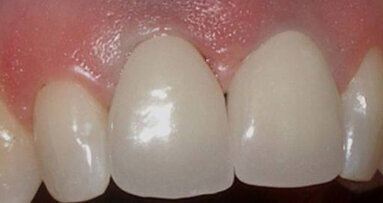

Fig. 11: Abutment. (Photo: Jens Tartsch, DMD)